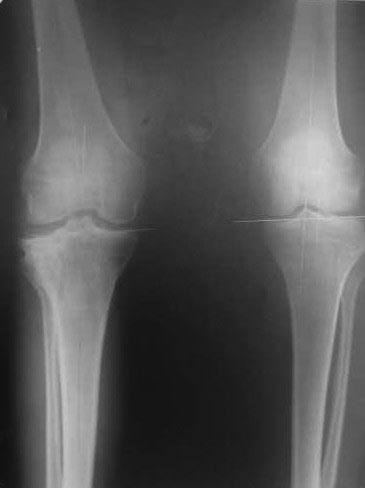

Здравствуйте коллеги,К нам обратилась девушка 17-ти лет с вальгусной деформацией

правого коленного сустава

Из анамнеза : более года назад перелом тибиального плато большеберцовой кости вследствие

ДТП. Была прооперирована в одной из клиник. На сегодняшний день: вальгусная деформация

правого коленного сустава, сгибательная контрактура 0-15-130гр. Планируем провести

коррегирующую остеотомию (open wedge) с замещением дефекта аллотрансплантатом и

фиксацией пластиной. Буду очень благодарен за Ваши советы, С уважением Ihor.